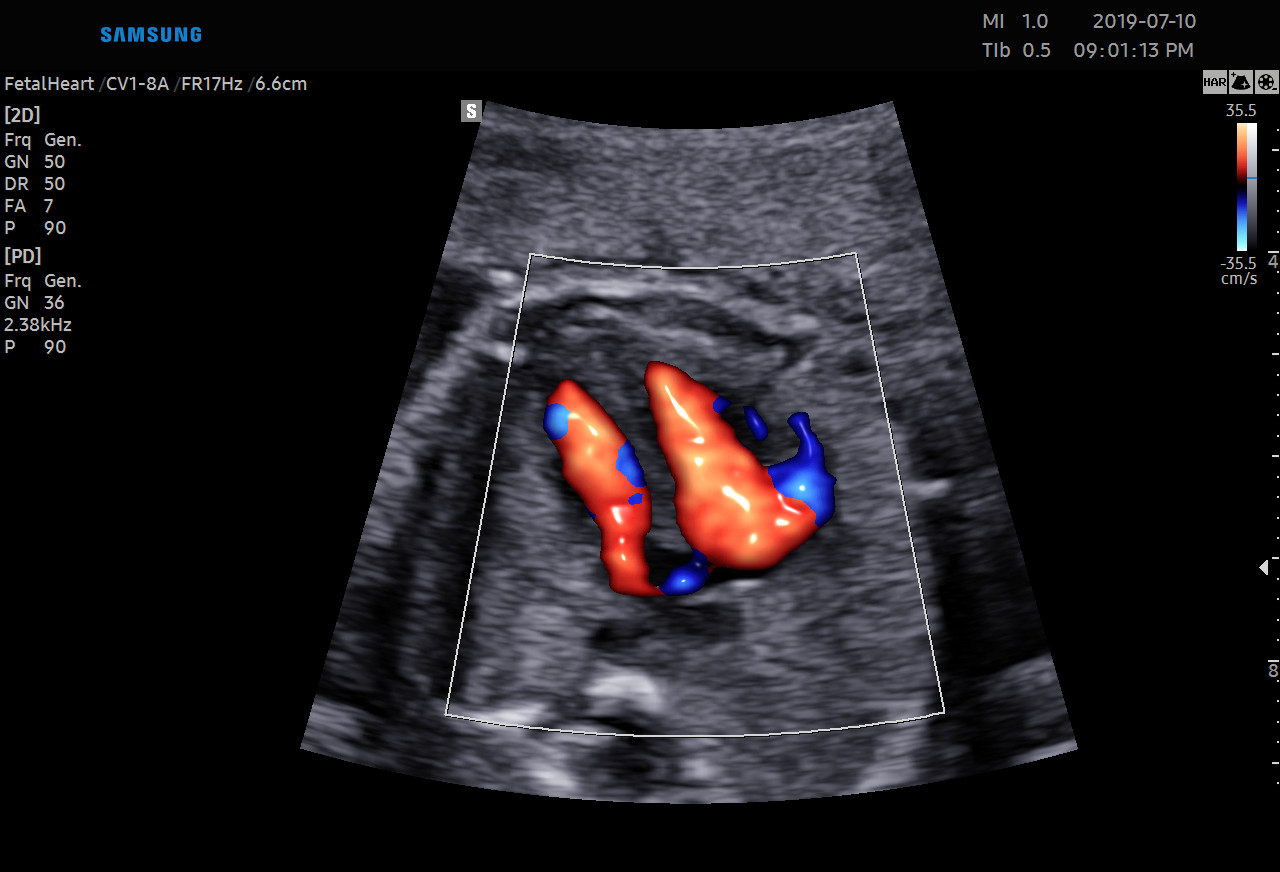

Diagnostykę obrazową przeprowadzamy z wykorzystaniem sprzętu Samsung HERA W9. To najnowszy aparat klasy premium – z kompletem głowic USG wysokiej rozdzielczości w tym głowicą USG 3D/4D. Doskonała jakość obrazu przekłada się na wiarygodność wyników.

Dostęp do nowoczesnej aparatury pozwala na obrazowanie przepływów w naczyniach krwionośnych. Dlatego wykonujemy również badania USG Doppler:

Ponadto jesteśmy w stanie zmierzyć przepływy w naczyniach u kobiet ciężarnych oraz płodu.